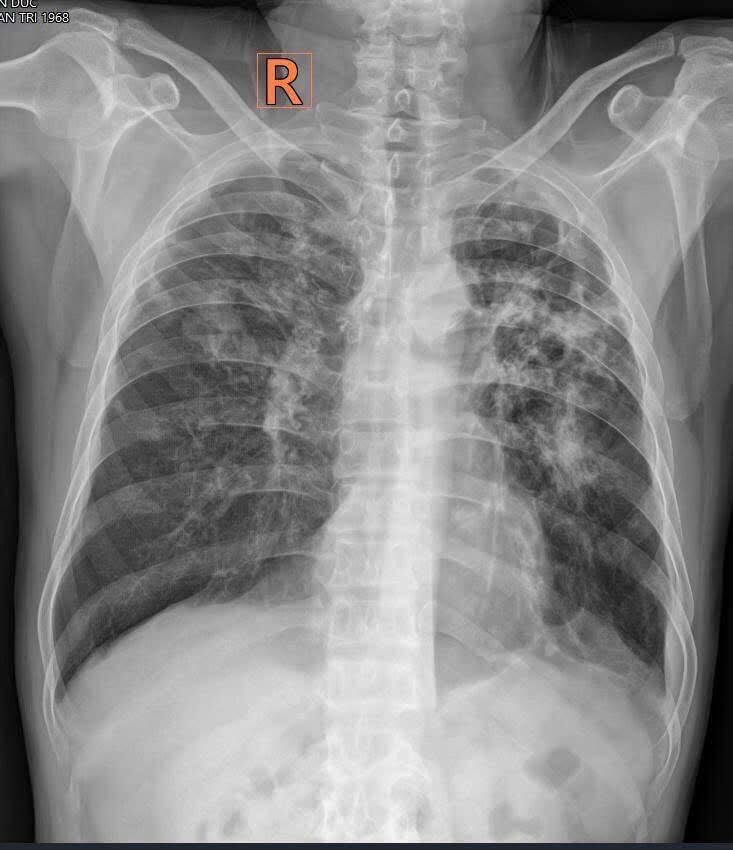

Trên diễn đàn Tự học CĐHA có đưa 1 phim XQ phổi. Bn 51t. Ho kéo dài, đờm nâu, gần đây sút cân….

- Lồng ngực cân đối. Phổi trái giảm thể tích nhẹ. Tổn thương có mặt cả 2 phổi.

- Phổi phải: hình ảnh tổn thương ưu thế thuỳ trên, các đám mờ thâm nhiễm, chúng có ranh giới rõ, nhiều vệt tăng cản dạng xơ hóa,

Kèm co kéo rốn phổi và giãn thể tích phổi: lá màng phổi đẩy sâu vào giữa cột sống. Ổ viêm cũ dạng đông đặc vùng góc tâm hoành.

- Phổi trái: tổn thương tập trung dày đặc hơn ở thuỳ trên, tăng cản xơ hóa mạnh, ứ khí vùng đỉnh, có hình vài hang với bờ dày mỏng khác nhau ( biểu hiện hang cũ có, và hang mới tạo ra có). Tổn thương còn thấy ở đáy phổi với hình ảnh viêm mảng cũ dính và ít dịch cũ của màng phổi.

Tóm tắt: Tổn thương 2 phổi có kiểu hình tương đồng, ưu thế thuỳ trên, xơ hóa, co kéo mạnh, có các hang nhỏ bên trái…

Kiểu hình lao phổi.